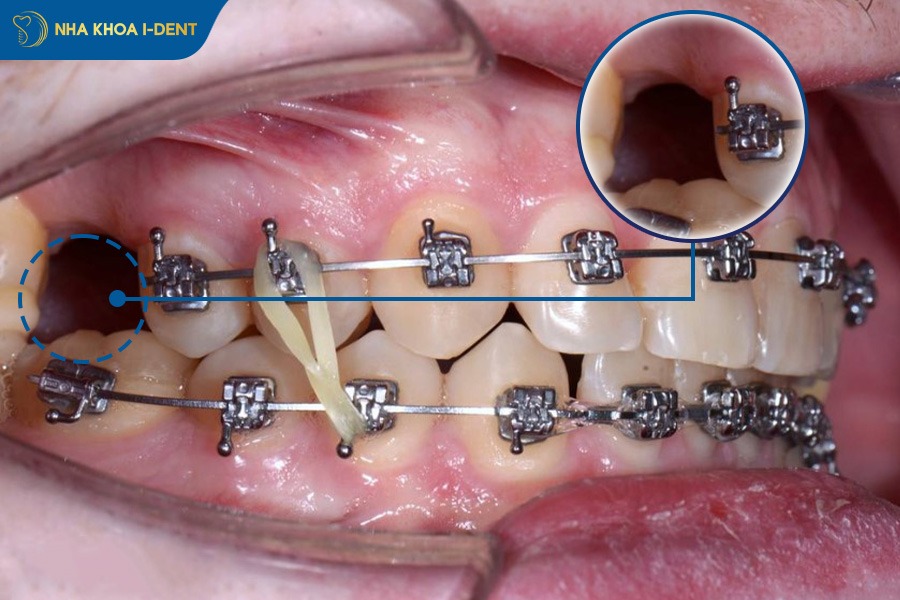

- Sử dụng minivis: Minivis được cắm vào xương hàm để tạo điểm neo chắc chắn, giúp bác sĩ kéo toàn bộ khối răng về phía sau một cách hiệu quả. Kỹ thuật này thường được áp dụng thay thế cho nhu cầu nhổ răng cối nhỏ trong các ca hô nhẹ đến nặng.

- Tận dụng khoảng nhổ răng khôn: Bác sĩ sẽ tận dụng khoảng trống từ việc nhổ răng khôn thay vì nhổ răng số 4 hoặc số 5 để kéo toàn bộ hàm răng lùi về sau.